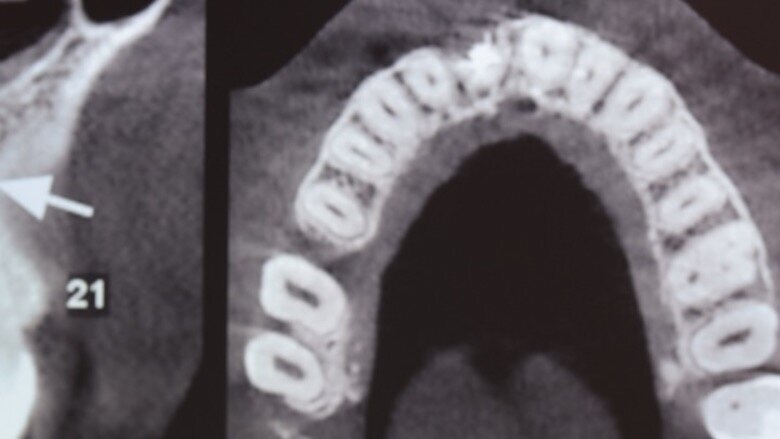

Figuras 2 y 3. Imágenes de tomografía CBCT donde se observa el grado de destrucción de la pared vestibular.